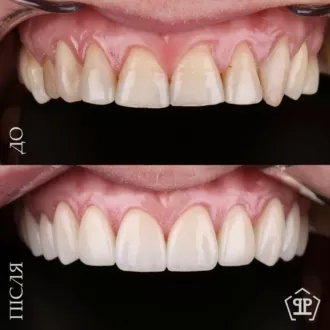

Произведена комплексная эстетическая реабилитация улыбки. Восстановлены правильные пропорции зубов, улучшено цвет и форму, гармонизирована улыбка с чертами лица. Сохранен максимальный объем собственных тканей — достигнут естественный и гармоничный результат.